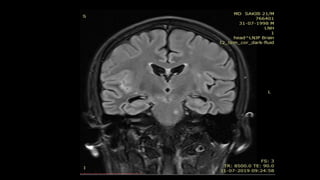

• #84  These are the axial T2WI taken at sequential intervals of a patient with R MCA territory infarct showing T2 fogging phenomenon with decrease in the the signal intensity over the period of time almost reaching to isointensity in 3rd image

• #85 CORONAL FLAIR IMAGE OF THE SAME PT SHOWS HYPERINTENSE SIGNAL